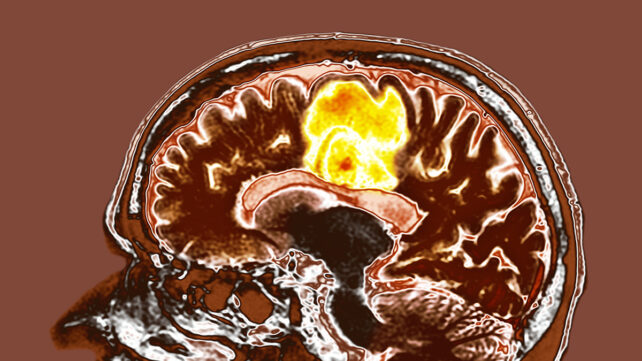

Glioblastoma is a particularly aggressive cancer, but encouraging results from a new study testing two common supplements on glioblastoma tumors could potentially lead to a new way to treat the disease.

Given glioblastoma's poor survival rates, scientists are trying to find new and improved ways to tackle these tumors, and this study might provide another avenue to explore.